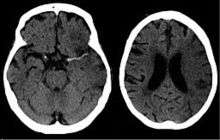

A CT showing early signs of a middle cerebral artery stroke with loss of definition of the gyri and grey white boundary

Dens media sign in a patient with middle cerebral artery infarction shown on the left. Right image after 7 hours.